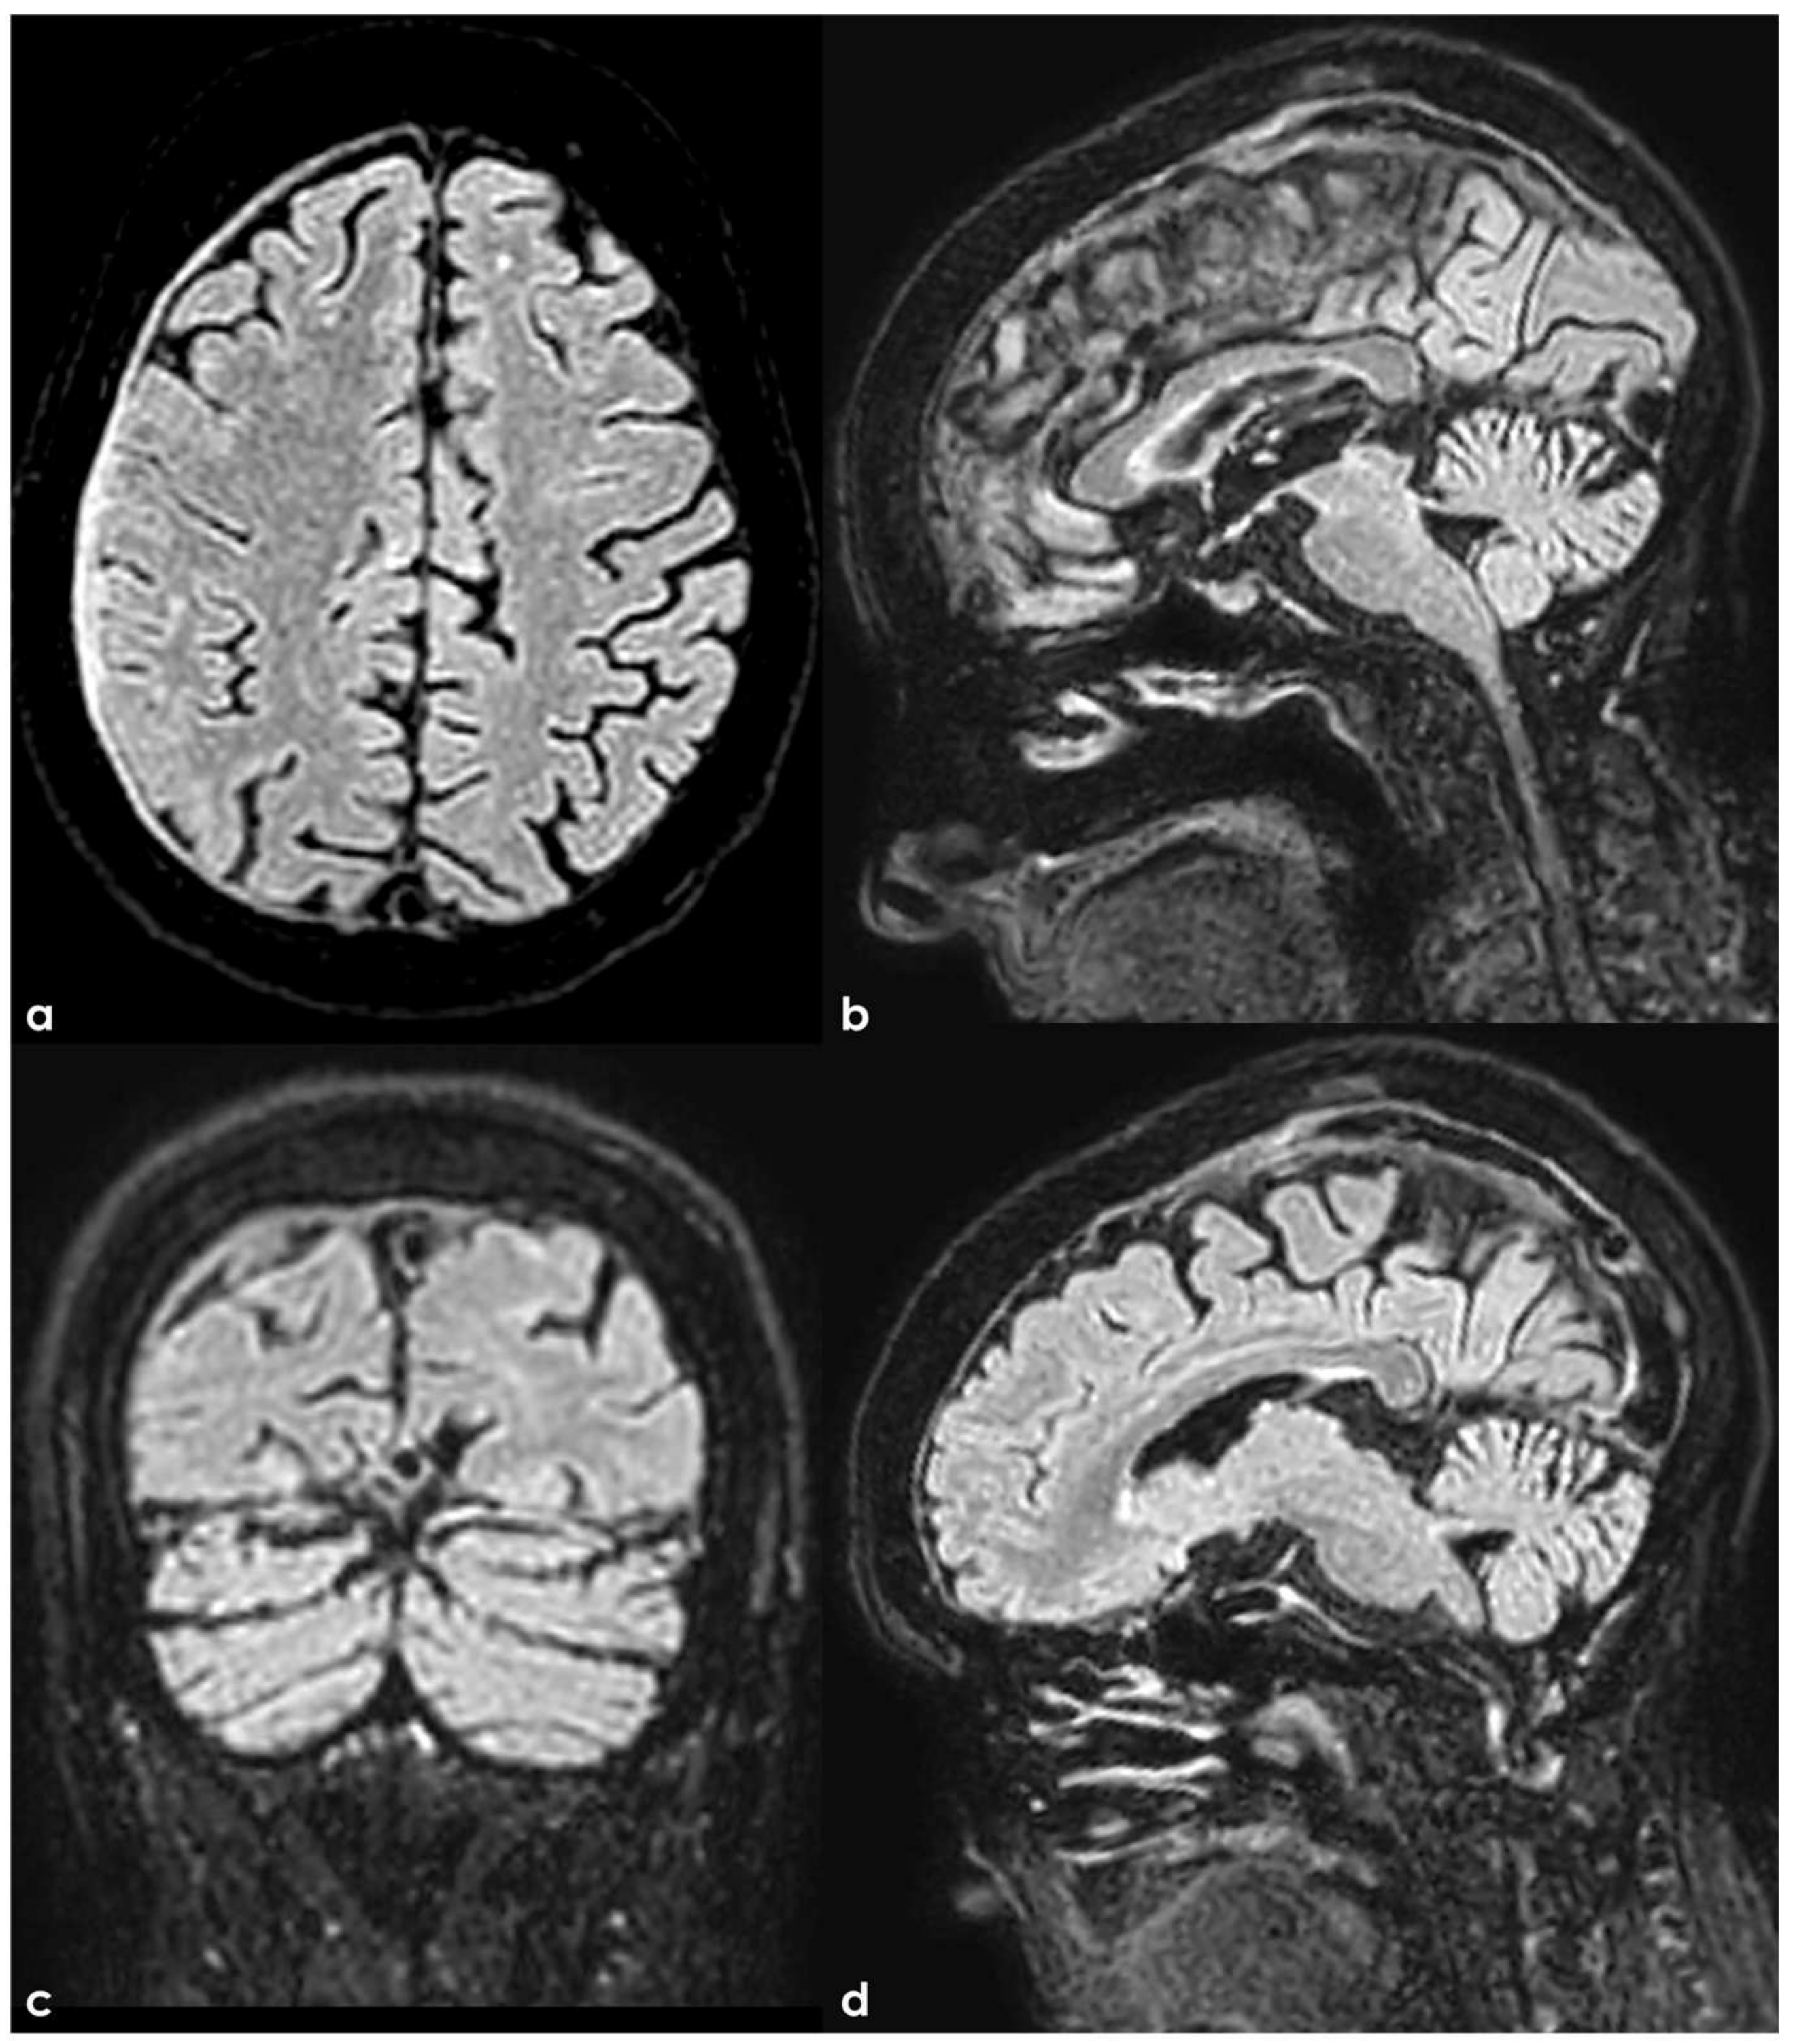

4.3.1. Superior Sagittal Sinus Variations

- San Millan Ruiz, D.; Fasel, J.H.D.; Gailloud, P. Unilateral hypoplasia of the rostral end of the superior sagittal sinus. AJNR Am. J. Neuroradiol. 2012, 33, 286–291. [Google Scholar] [CrossRef]

- Kocak, B.; Hasiloglu, K.O.; Kocer, N.; Aydin, S.; Islak, C. Total agenesis of superior sagittal sinus and falx cerebri in a patient who has a subacute subdural hematoma crossing midline: Case report. Neurosurgery 2013, 5, 863–867. [Google Scholar] [CrossRef]

- Kaplan, H.A.; Browder, J. Atresia of the rostral superior sagittal sinus: Substitute parasagittal venous channels. J. Neurosurg. 1973, 38, 602–607. [Google Scholar] [CrossRef] [PubMed]

- Manoj, K.S.; Krishnamoorthy, T.; Thomas, B.; Kapilamoorthy, T.R. An incidental persistent falcine sinus with dominant straight sinus and hypoplastic distal sagittal sinus. Pediatr. Radiol. 2006, 36, 65–67. [Google Scholar] [CrossRef] [PubMed]